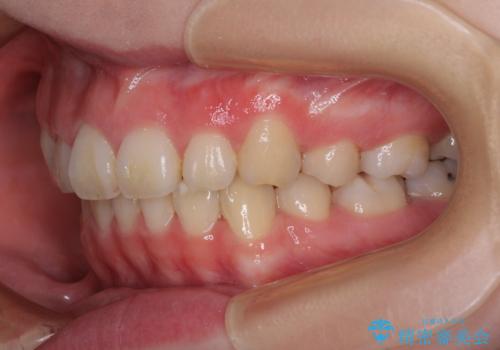

目立たない装置で出っ歯を治したい ハーフリンガル矯正

- 口元の突出感を気にして来院された患者様です。

上下左右の第一小臼歯4本を抜歯して口元を下げる治療計画としました。

目立たない装置が希望であったため、上顎が裏側装置である、ハーフリンガル装置を選択されました。